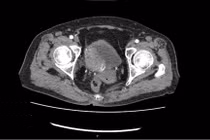

Phương pháp phẫu thuật nội soi cắt bàng quang tận gốc, đồng thời tái tạo bàng quang để điều trị triệt để ung thư đảm bảo chữa lành bệnh mà không ảnh hưởng đến chất lượng cuộc sống.